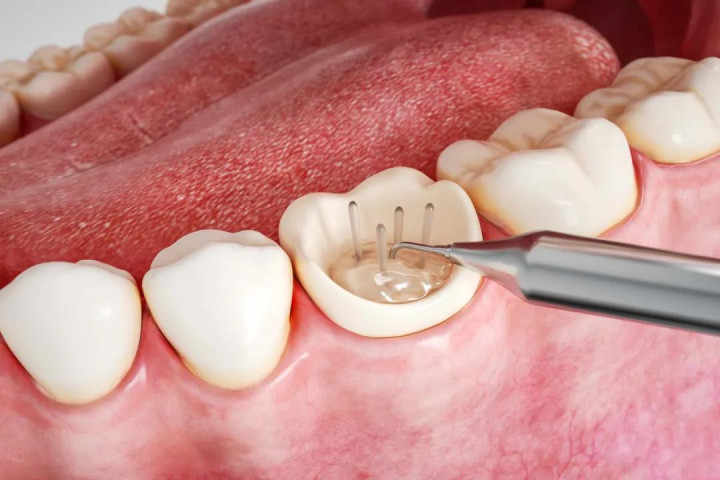

根管诊治!

医师需要大开牙齿,用挑升的器械把根管内坏死的牙髓组织和细菌算帐干净,消毒、填充,从“根”上根除感染。之后,经常需要作念一个牙冠把患牙保护起来。独一根管诊治身手保住这颗牙!